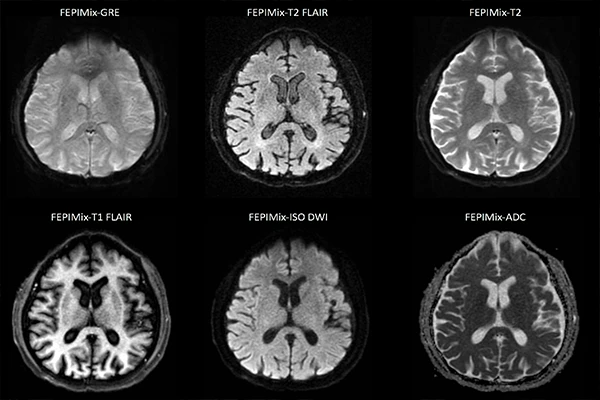

Understanding MRI Sequences: A Guide to T1, T2, FLAIR, and DWI

A deep dive into common MRI sequences, what tissues they highlight, and their clinical uses.